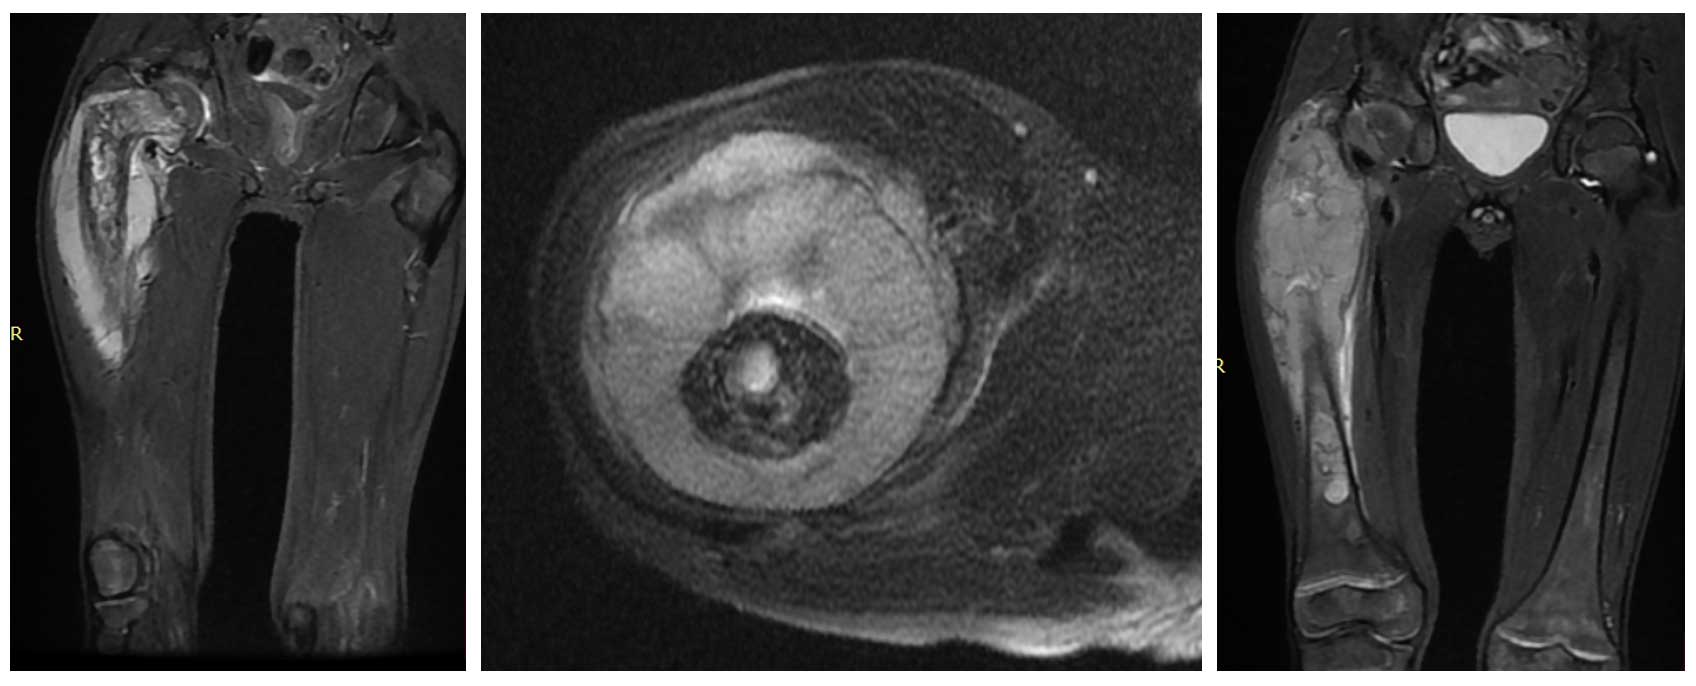

Ameliyat Öncesi: Tümörün femur başından distale kadar uzandığı ve proksimalde çepeçevre büyükçe heterojen yumuşak doku kitlesinin eşlik ettiği görülmekte.